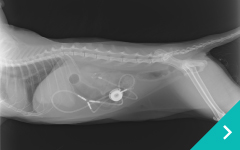

「血液透析」「結石破砕装置」「2.8mm細径内視鏡」 「SUBシステム」「尿管ステント」を組み合わせる事により、今までにない新たな治療に取り組んでいきます。

SUBシステム

SUB

システム

ステント治療

ステント

治療